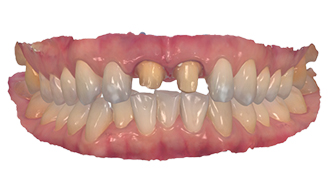

Zirconia Crowns:

For durable and aesthetically pleasing dental restorations, werecommend Zirconia Crowns, a type of tooth restoration treatment that covers severe decay and bad discoloration. Zirconia is a strong and biocompatible material that closely resembles the natural appearance of teeth. Our dental experts craft zirconia crowns with precision and artistry, ensuring a perfect fit and a seamless blend with your existing teeth. With zirconia crowns, you can achieve strong teeth and a pleasant smile.